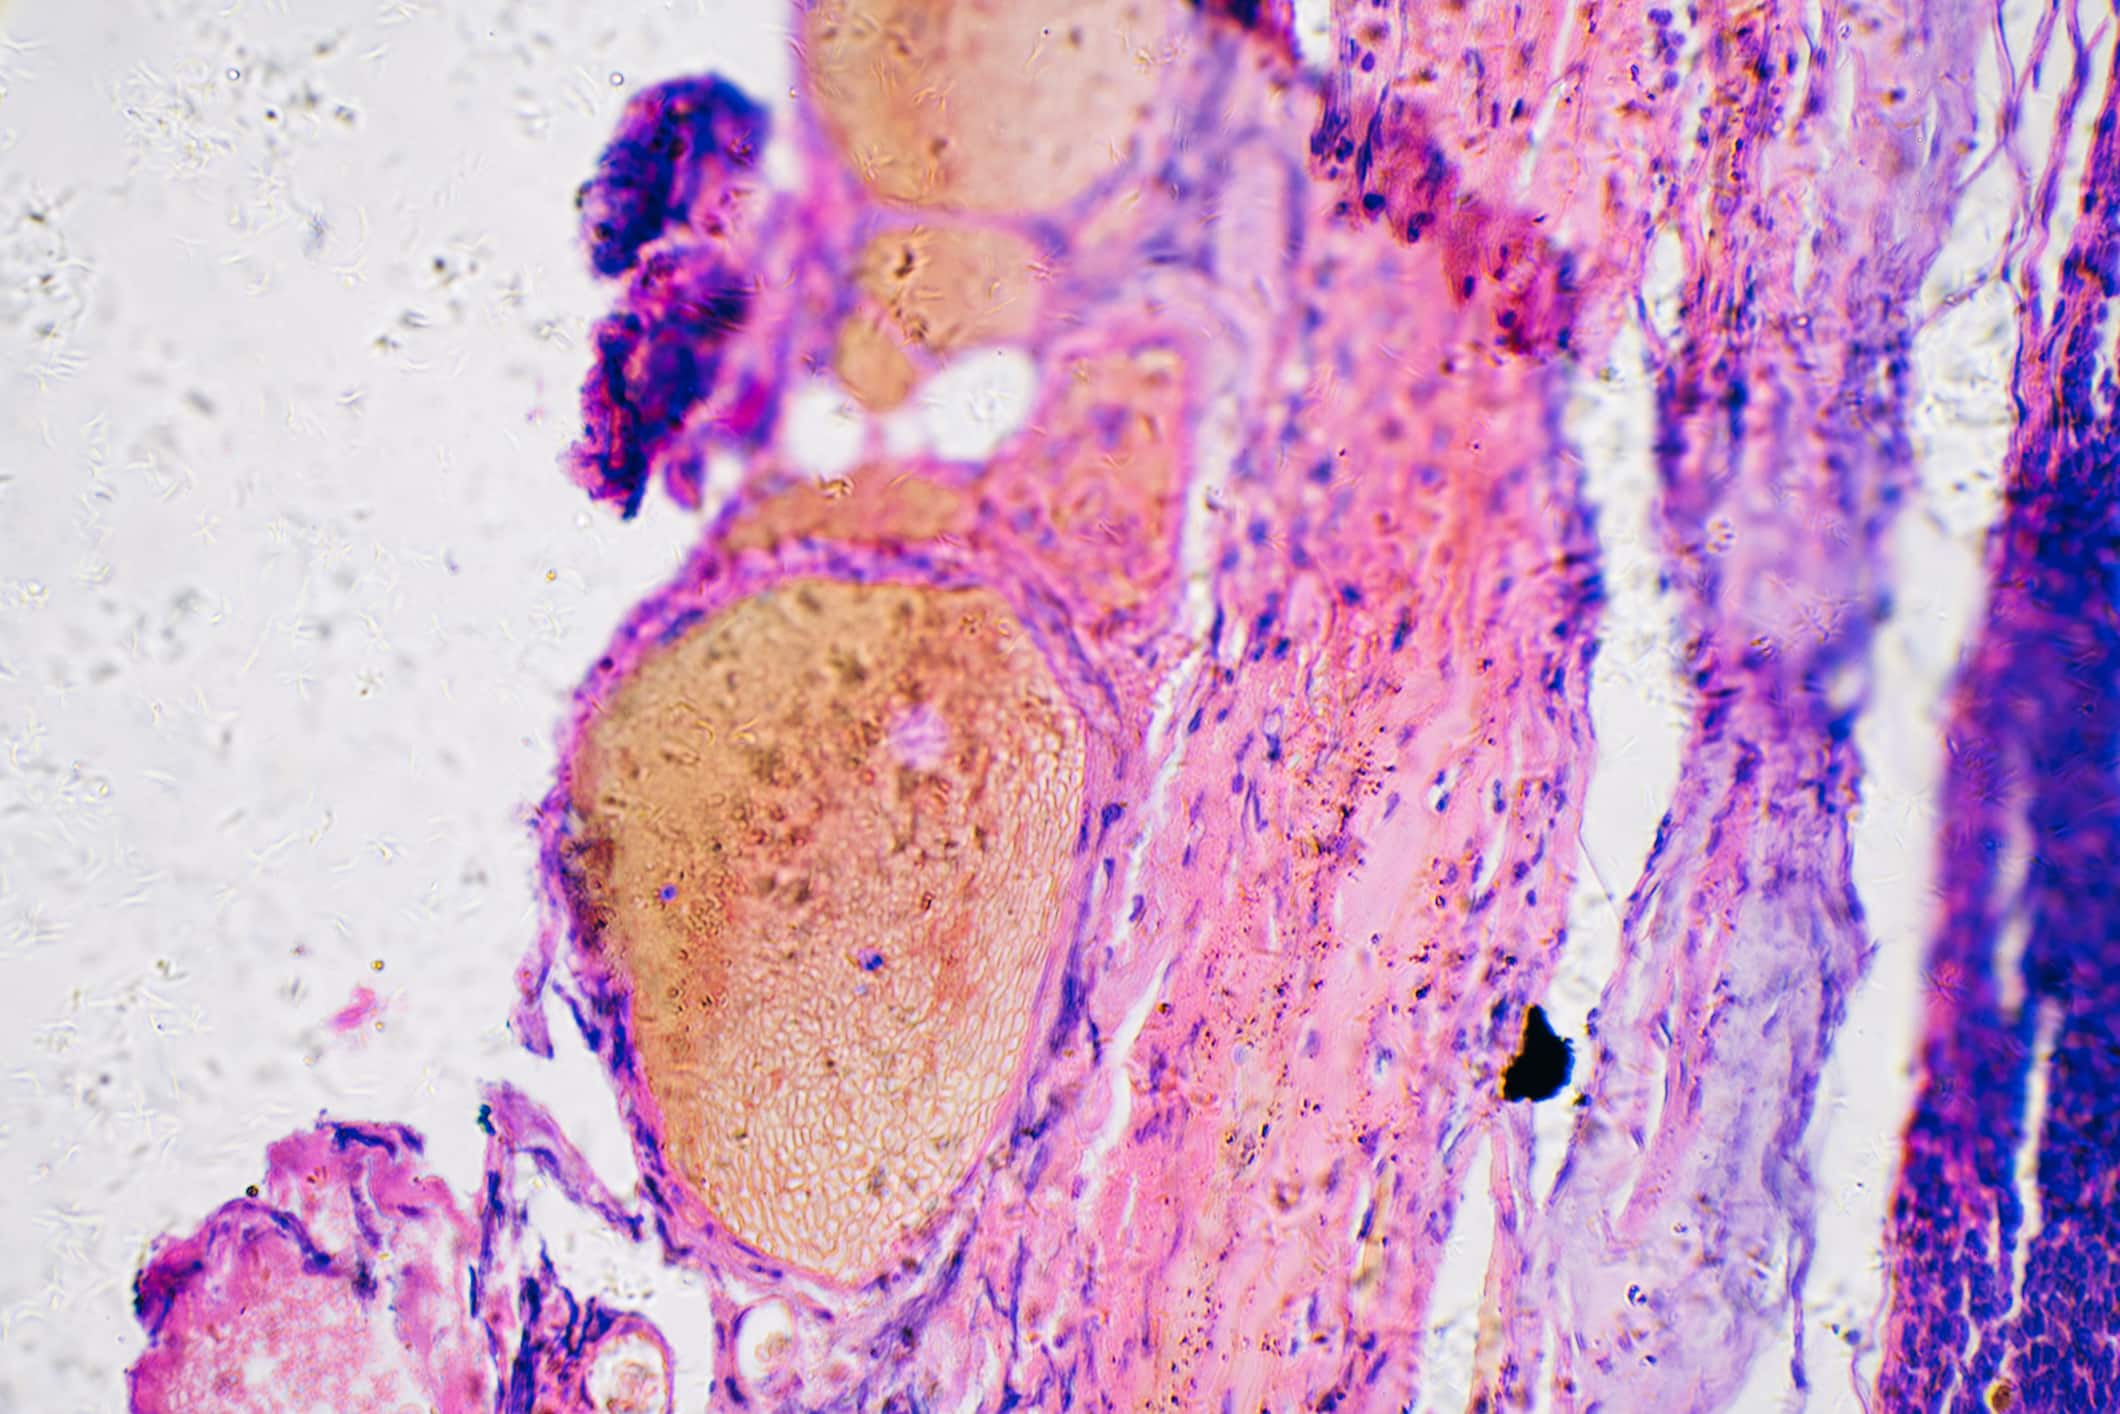

Melanocytes & Moles

Melanocytes produce melanin, the pigment that gives skin its natural color. When skin is exposed to the sun, melanocytes produce more pigment, causing the skin to tan, or darken.

Sometimes, clusters of melanocytes and surrounding tissue form noncancerous growths called moles. (Doctors also call a mole a nevus; the plural is nevi.) Moles are very common. Most people have between 10 and 40 moles. Moles may be pink, tan, brown, or a color that is very close to the person’s normal skin tone. People who have dark skin tend to have dark moles. Moles can be flat or raised. They are usually round or

oval and smaller than a pencil eraser. They may be present at birth or may appear later on—usually before age 40. They tend to fade away in older people.